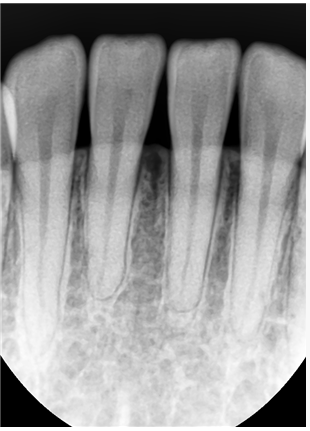

앞니 1개의 치아 뿌리가 다른 것보다 짧습니다. 이런 경우 교정을 하면서 치아에 힘을 주면 치아 뿌리가 더 짧아지는 치근흡수가

일어날 가능성이 있습니다. 그러나 꼭 교정을 하시고 싶으면 교정하는 것도 큰 무리가 아닐 수도 있습니다. 양악수술은 큰 수술이며

치아에 과도한 교합력이 가해지메 되면 치아의 뿌리가 흡수되는 경우가 있습니다.

현재 상악 전치와 하악 전치의 뿌리의 길이가 정상적인 것보다 짧기 때문에 무리하게 후방견인을 하다가 치아 뿌리가 더 짧아지게 되면 나중에 잇몸뼈의 높이가 낮아지게 되었을 경우에 조기에 상실할수 있는 가능성이 있습니다.